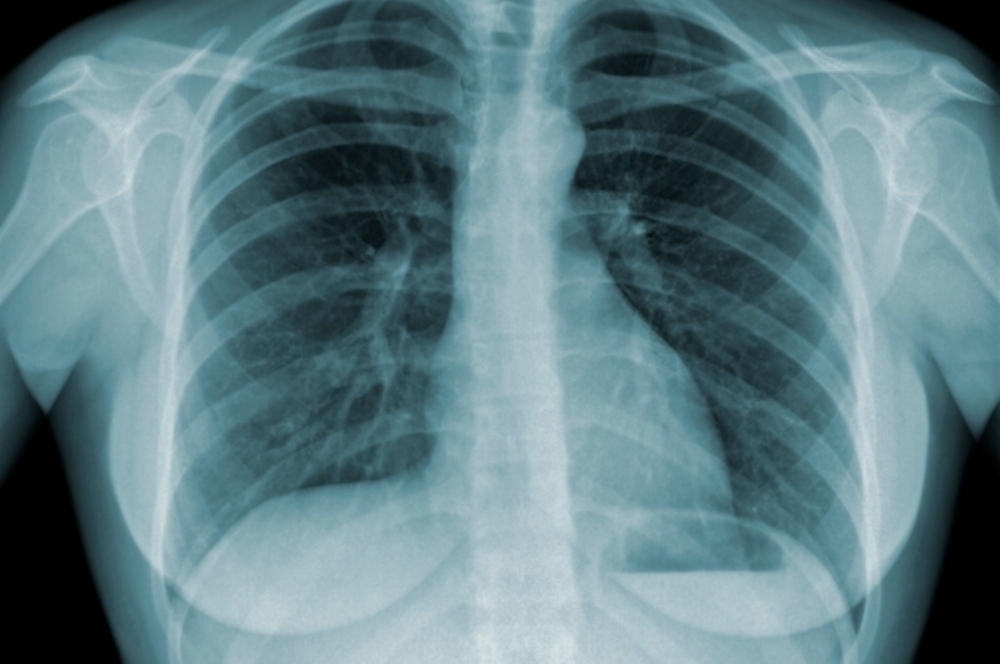

| É necessário ficar atento aos sintomas da tuberculose para dar início ao tratamento (foto: arquivo SES) |

A tuberculose se caracteriza pela infecção do chamado bacilo de Koch, entre outros agentes, e é transmitida pelo ar. A pessoa infectada pela tuberculose pulmonar tem geralmente os seguintes sintomas: tosse constante por duas ou três semanas, escarro (às vezes com presença de sangue), dor no peito, fraqueza, perda de apetite, de peso, febre e sudorese. Nos casos em que a tuberculose afeta outros órgãos, os sintomas podem variar.